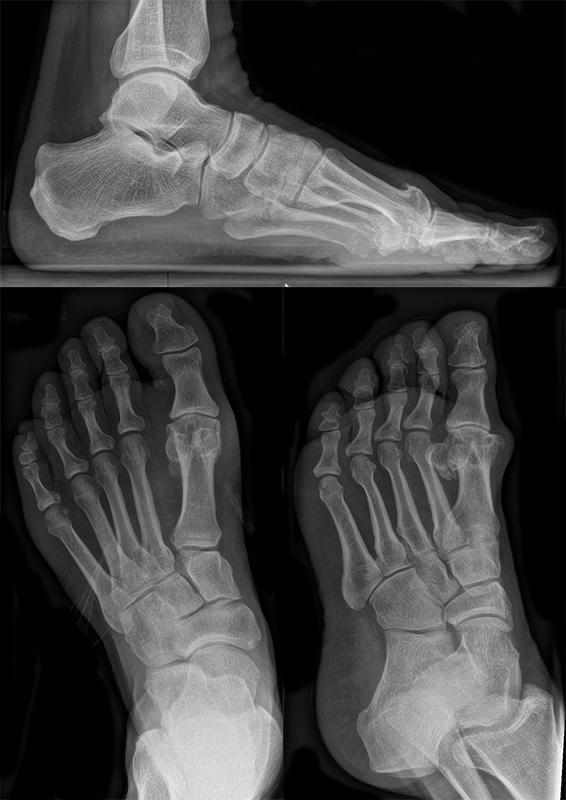

• Röntgen: Fuß belastet in 3 Ebenen.

• Optional MRT und CT bei radiologisch unklaren Verhältnissen.

Zum Lesen der Bildbeschreibung und zur Vollansicht bitte das Bild anklicken (Foto: M. Walther).